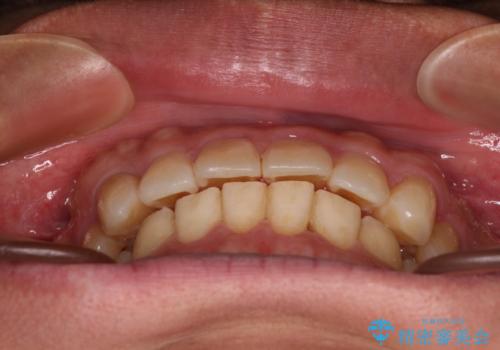

- 前歯のデコボコを気にして来院された患者様です。

当院でインビザライン矯正治療をされている方からのご紹介ということで、インビザラインでの矯正治療をご希望でした。

ワイヤー矯正に比べ来院頻度は低いものの、新幹線での通院のため、やや治療期間が延びることが懸念されました。